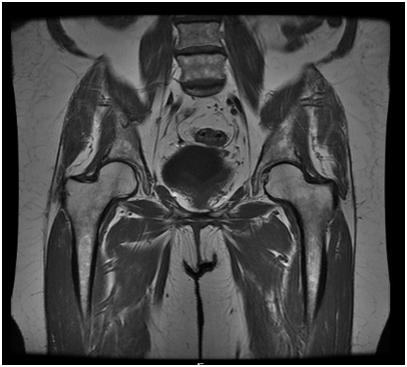

MRI of the Pelvis OB/GYN: Exam Description

Your doctor has ordered a MRI (Magnetic Resonance Imaging) of your pelvis. MRI uses a magnetic field, radio waves and a computer to create images soft tissues, bones, and internal body structures. MRI of the pelvis allows physicians to examine the pelvic anatomy to rule out any structural abnormalities.